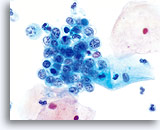

Cellules souvent disposées en petits groupes et en petits galets (environ 4 à 7 cellules). Ces groupes ont un aspect caractéristique et résultent d’une cohésion anormale (à ne pas confondre avec les “amas”, qui sont probablement le simple résultat de la traction exercée par l’instrument de prélèvement).60x

HSIL

Cellules souvent disposées en petits groupes et en petits galets (environ 4 à 7 cellules). Ces groupes ont un aspect caractéristique et résultent d’une cohésion anormale (à ne pas confondre avec les “amas”, qui sont probablement le simple résultat de la traction exercée par l’instrument de prélèvement).60x

Irrégularité de la polarité nucléaire. Lorsqu’ils forment des groupes, les noyaux de haut grade présentent une perte de polarité ou une architecture chaotique ; leur taille et leur forme varient. Ils ont en outre peu de respect pour leurs voisins. 60x

HSIL

Irrégularité de la polarité nucléaire. Lorsqu’ils forment des groupes, les noyaux de haut grade présentent une perte de polarité ou une architecture chaotique ; leur taille et leur forme varient. Ils ont en outre peu de respect pour leurs voisins. 60x